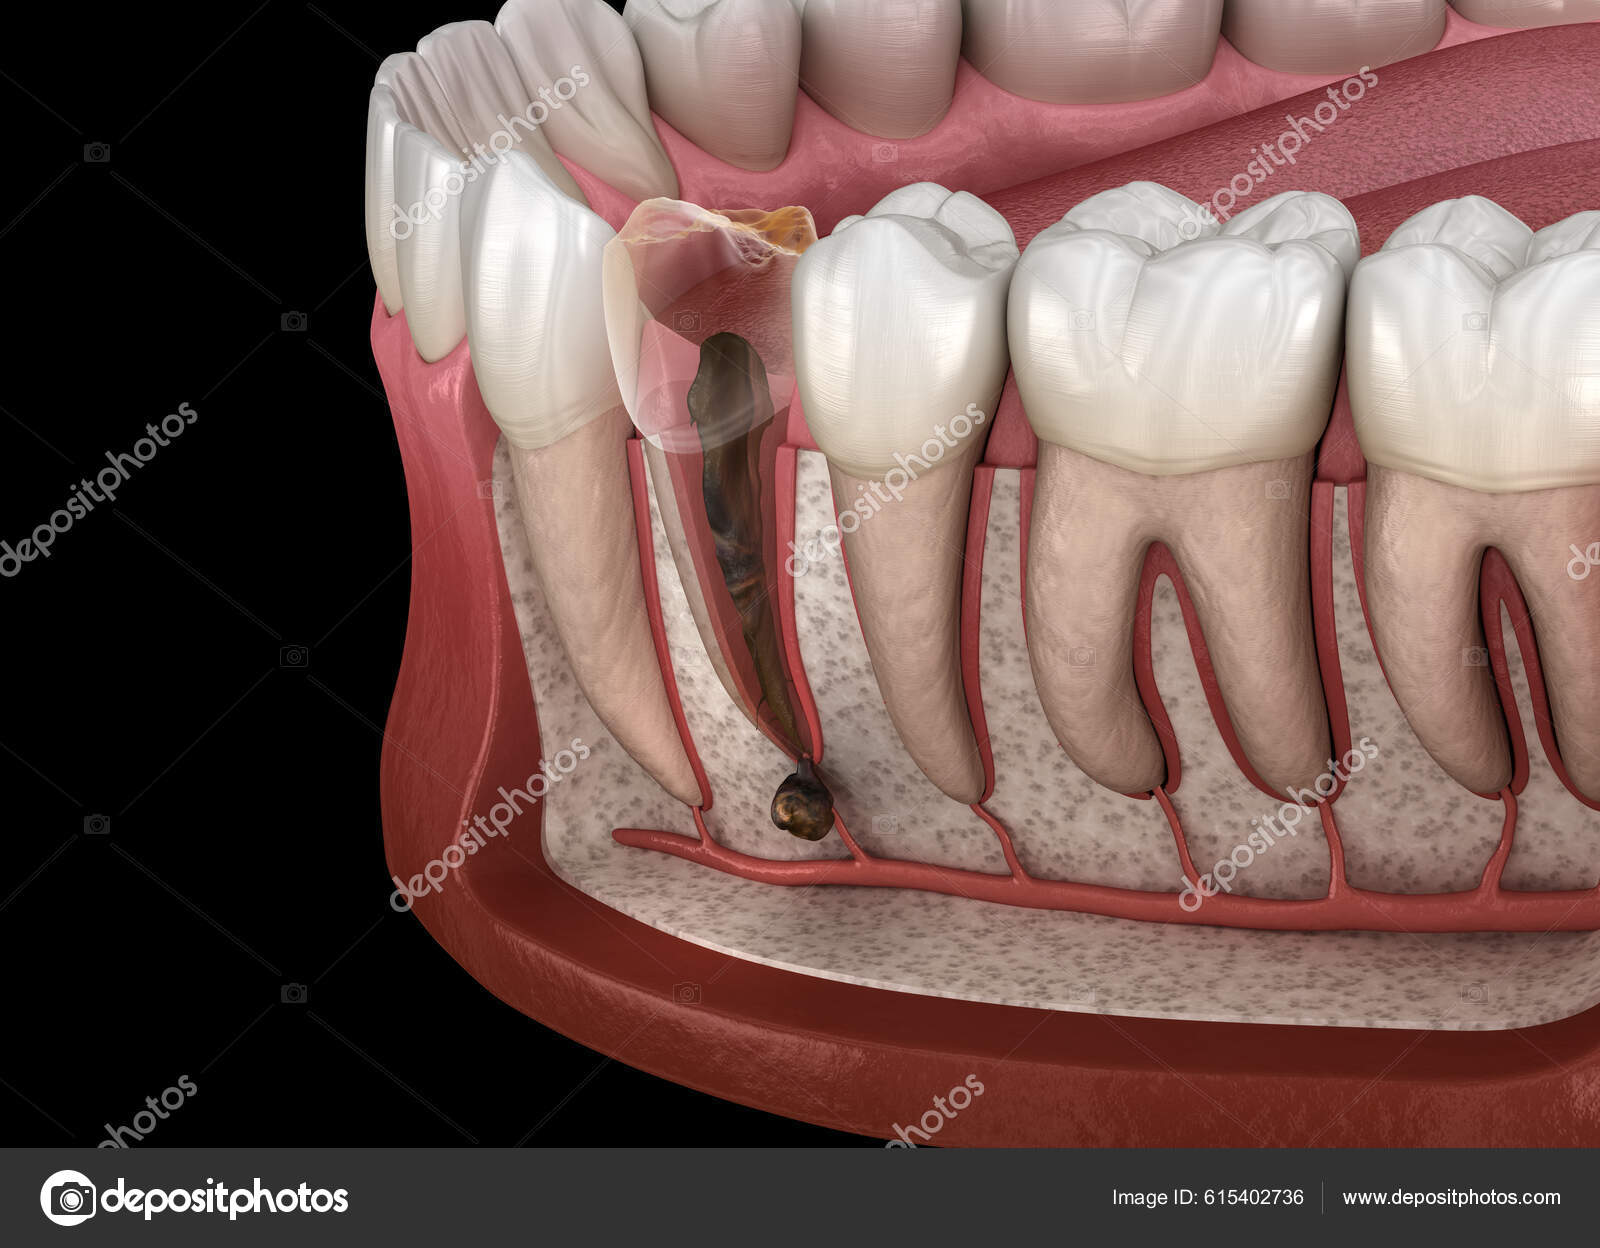

From depositphotos.com

Periostitis Tooth Lump Gum Tooth Medically Accurate Dental Illustration Periostitis Jaw What are the clinical and histologic features of proliferative periostitis? What are the histologic and. — chronic osteomyelitis with proliferative periostitis is a rare form of osteomyelitis that is characterised by new. — proliferative periostitis is a rare disease, and represents new bone formation with periosteal reaction. — a total of 156 patients with chronic osteomyelitis, proliferative. Periostitis Jaw.